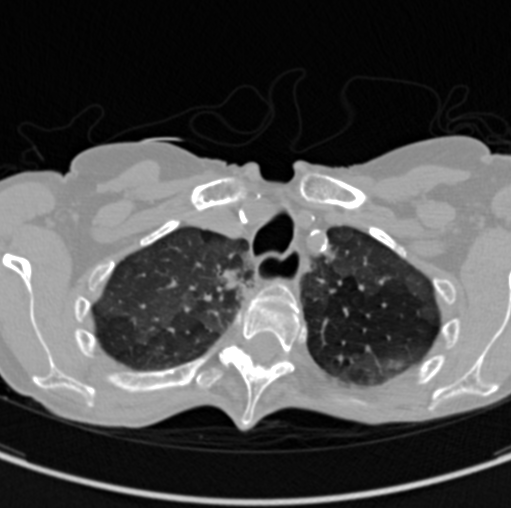

COVID-CTPRED is a comprehensive cohort database gathering an enhanced and

comprehensive chest-CT imaging together with biological,patient history, risks factors, and current clinical data.

Computational medical imaging alone has shown its ability to predict a therapeutic response

or a particular evolution after extracting from the volume of images informations that are

not visually perceptible during standard radiological reading, making it possible to construct

a radiomic signature and/or using anatomical/functional metrics.

By combining these data extracted from the scanner with the standard clinical-biological

data produced at admission during triage, our ambition is to build more representative

predictive models to anticipate clinical evolution and to optimize the management of the

resources